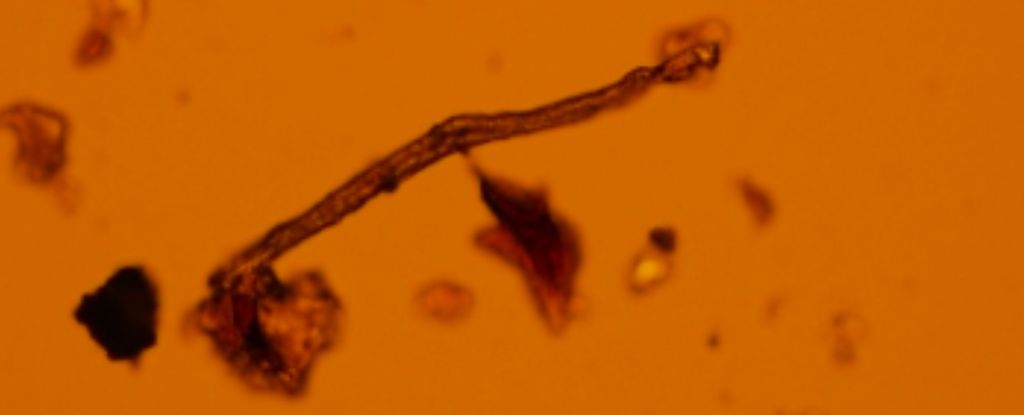

Pred tromi rokmi vedci prvýkrát objavili mikroplasty plávajúce v štyroch rôznych ľudských placentách, a ako sa ukázalo, bola to len špička ľadovca. Začiatkom roku 2023 výskumníci oznámili, že našli mikroskopické častice plastového odpadu v najmenej 17 rôznych placentách. Pomocou novej techniky teraz výskumníci identifikovali drobné častice a vlákna plastu s veľkosťou menšou ako mikrón v doteraz najväčšej vzorke placent.

Po použití na 62 vzoriek placenty technika odhalila, že viac ako polovica všetkých plastov nájdených v placente je polyetylén – najčastejšie používaný plast na našej planéte, z ktorého sa vyrábajú napríklad jednorazové tašky a fľaše. Ďalšie plastové častice identifikované v placente zahŕňajú polyvinylchlorid, nylon a polypropylén, z ktorých všetky sú pravdepodobne staré niekoľko desaťročí, boli zvetrané a oxidované roky v prostredí predtým, ako ich ľudia vdýchli alebo prehltli.